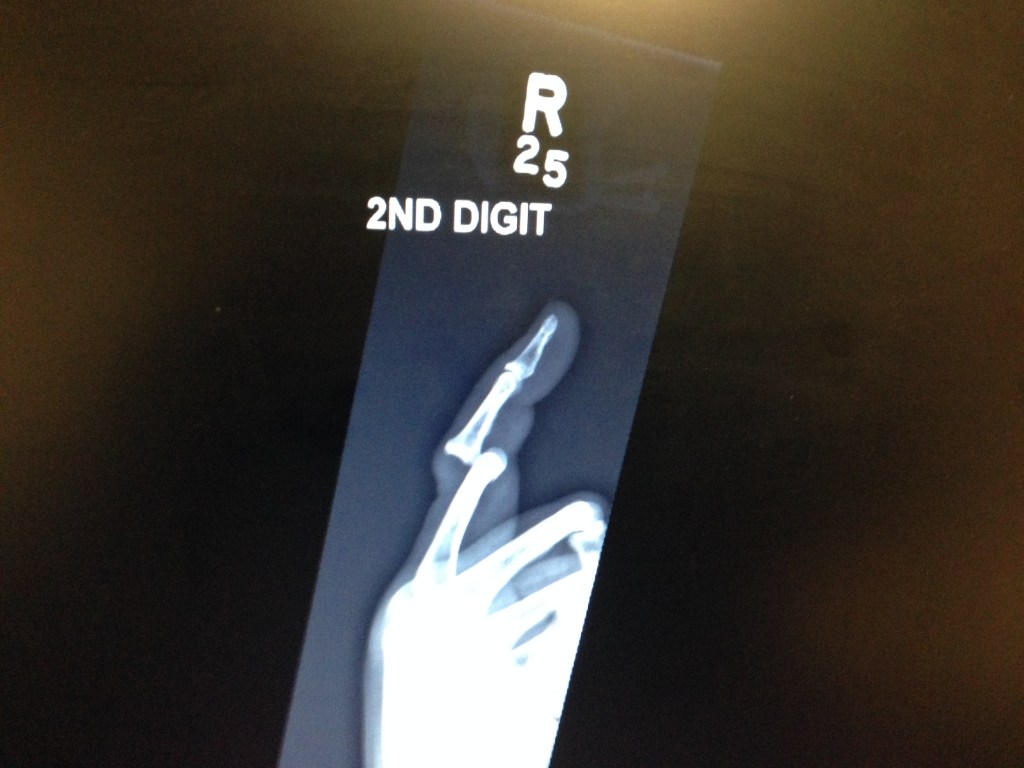

hoppin johnHoppin John which contains blackeye peas is traditionally served on New Years Eve/ Day. They are supposed to bring good luck. I guess I could use it since I fell the other day, it was my own fault, never, especially on the pot hole laden streets of NYC push a shopping cart in front of you, you should drag it in back. I learned the hard way, I had just come from the food coop, cart full of all sorts of good stuff, it was pretty heavy. Crossing the street walking at a brisk pace, the wheels got stuck in a pothole, I went flying over the cart with my finger in one of the grooves, it completely dislocated my finger. I spent the rest of the day in the ER where they had to put it back together. I was lucky it wasn’t fractured. Unlucky for me it’s my right hand index finger. I will adapt. This was a bit difficult to make not because the recipe is hard but working without my index finger is not easy and painful.Vegetables are not cut in the proper size pieces but the results are the same.

Dislocated fingerSo I thought I better make some blackeye peas for good luck, this is not the way I envisioned starting 2014.